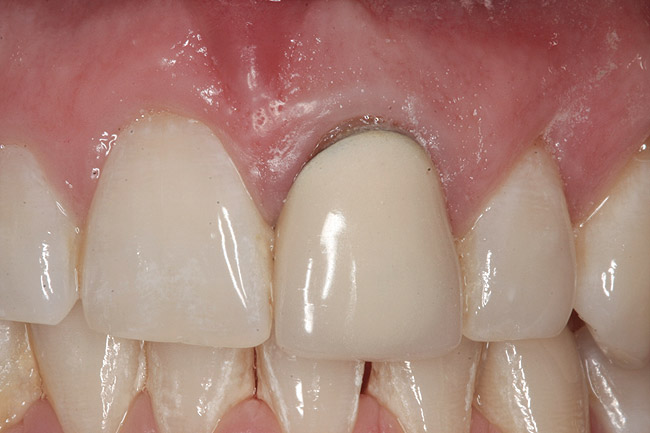

The provisional is then trimmed of flash and polished, placed into the mouth, and hand tightened. Blanching of the soft tissue is seen as the result of the tissue slumping without the support of the tooth (Figure 7). The provisional is evaluated for proper free gingival margin positioning. The interdental papilla are assessed for volume and height, and the occlusion is checked. If there are any shortcomings, the provisional contours are adjusted. If the gingival margins are more apical than ideal, the cervical area of the provisional is relieved. If the free gingival margin is more coronal than the ideal position, the cervical area of the provisional is bulked out to move the soft tissue apically. Interdental papilla are altered by changing the contact point position, volume, and convexity of the proximal surfaces.10,11 Once the esthetic contours have been developed, a cotton pellet is placed over the screw head, the access hole is filled in with the material of choice, and the occlusion is checked. The goal is to achieve minimal centric contact with no contact in lateral excursions.

Fig 7. Blanching of the soft tissue.

Figure 7